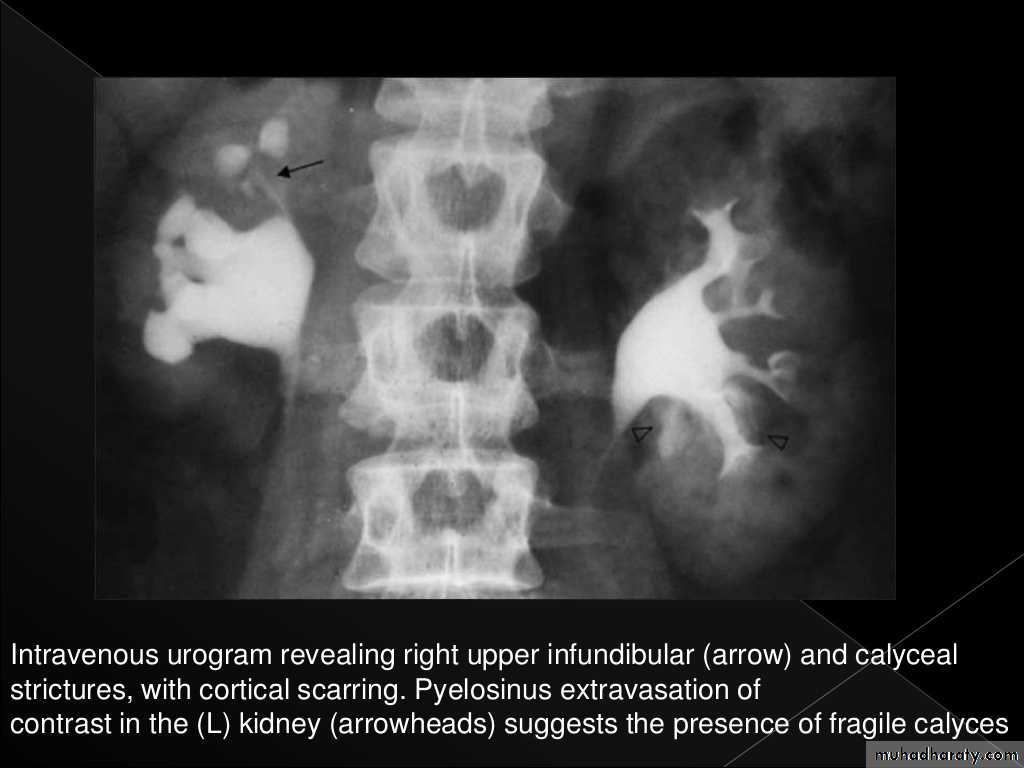

Cortical scarring

"Smudged" papillae (moth-eaten) –irregular due to inflammation and necrosis

Infundibular strictures

Hydrocalyces without dilatation of renal pelvis, or Hydronephrosis